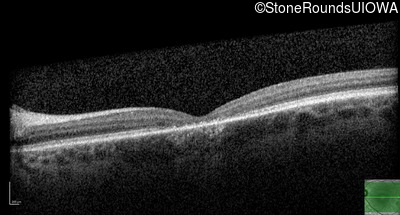

Age at visit: 17 years (Visit 2)

Age at visit: 21 years

Age at visit: 23 years

Age at visit: 25 years